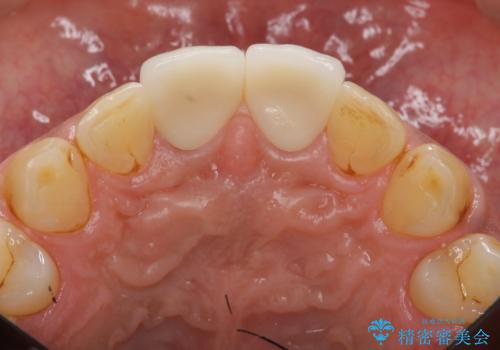

- 体調により前歯部の歯ぐきから出血や膿が出ることの改善を求めて来院されました。

X線写真より、根尖部に透過像が認められ根管治療・ファイバーコア築盛・セラミッククラウンの作製が必要な状態です。

- 46万円(仮歯・根管治療・ファイバーコア・ジルコニアクラウン×2)費用は治療当時の料金となります